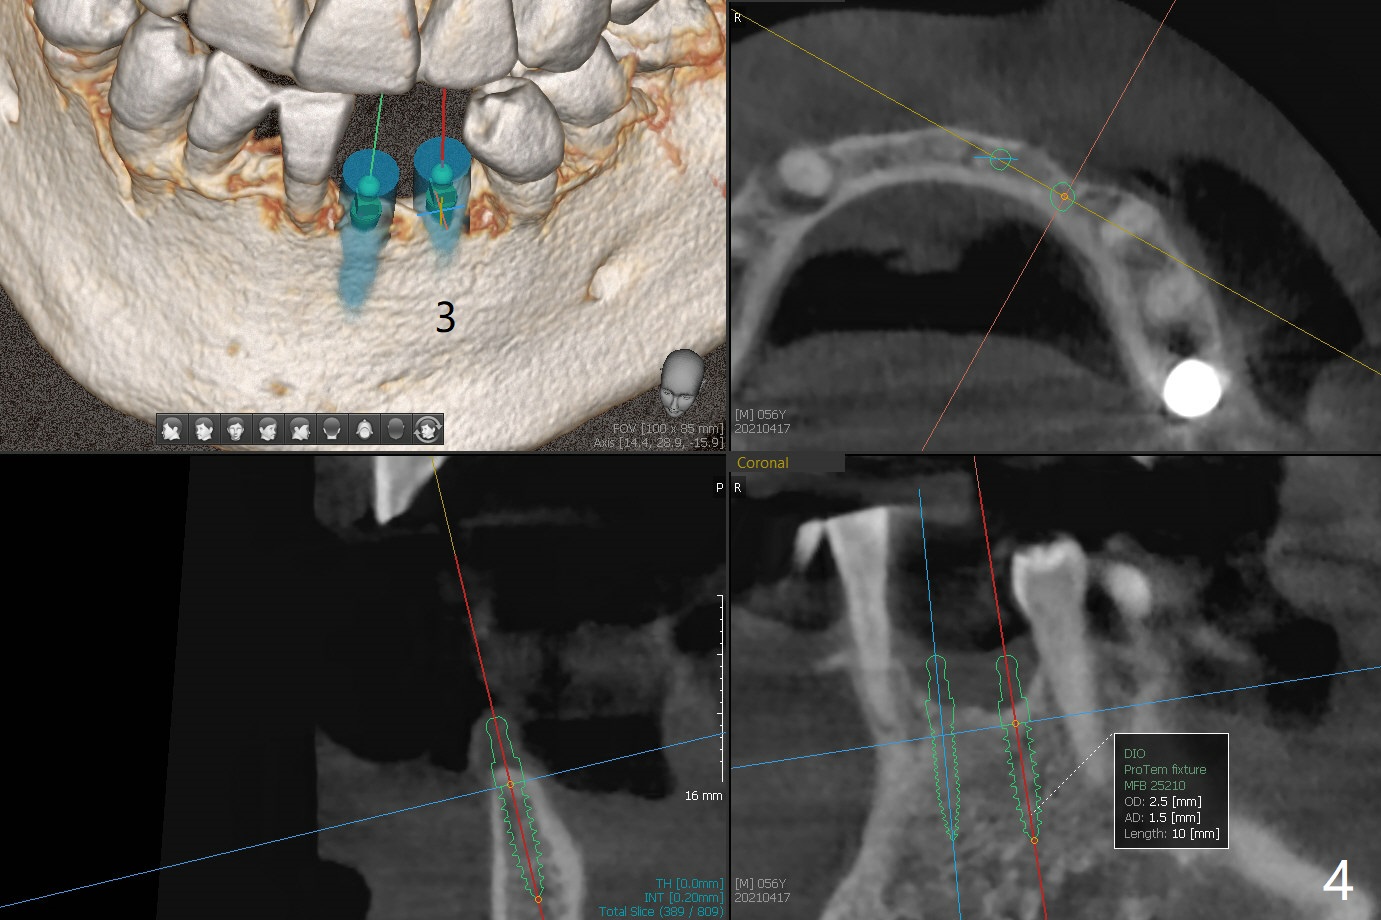

56岁男右下7位点保存一个月,还缺失4个牙齿(图一),左下2,3牙槽嵴特别狭窄,骨皮质为主(图二),应该植入2.0,2.5毫米植体(图三,四),避免复杂植骨术。而右上3骨质也狭窄,但是骨质密度低,几乎松质骨(图五),如果采纳骨膨胀术(高速倒转),植体可以大于4.0毫米,防止植体断裂。左上7骨质宽,但是短,5x8.5毫米植体可能胜任功能(图六)。如果植入10毫米植体,需要做上颌窦提升。